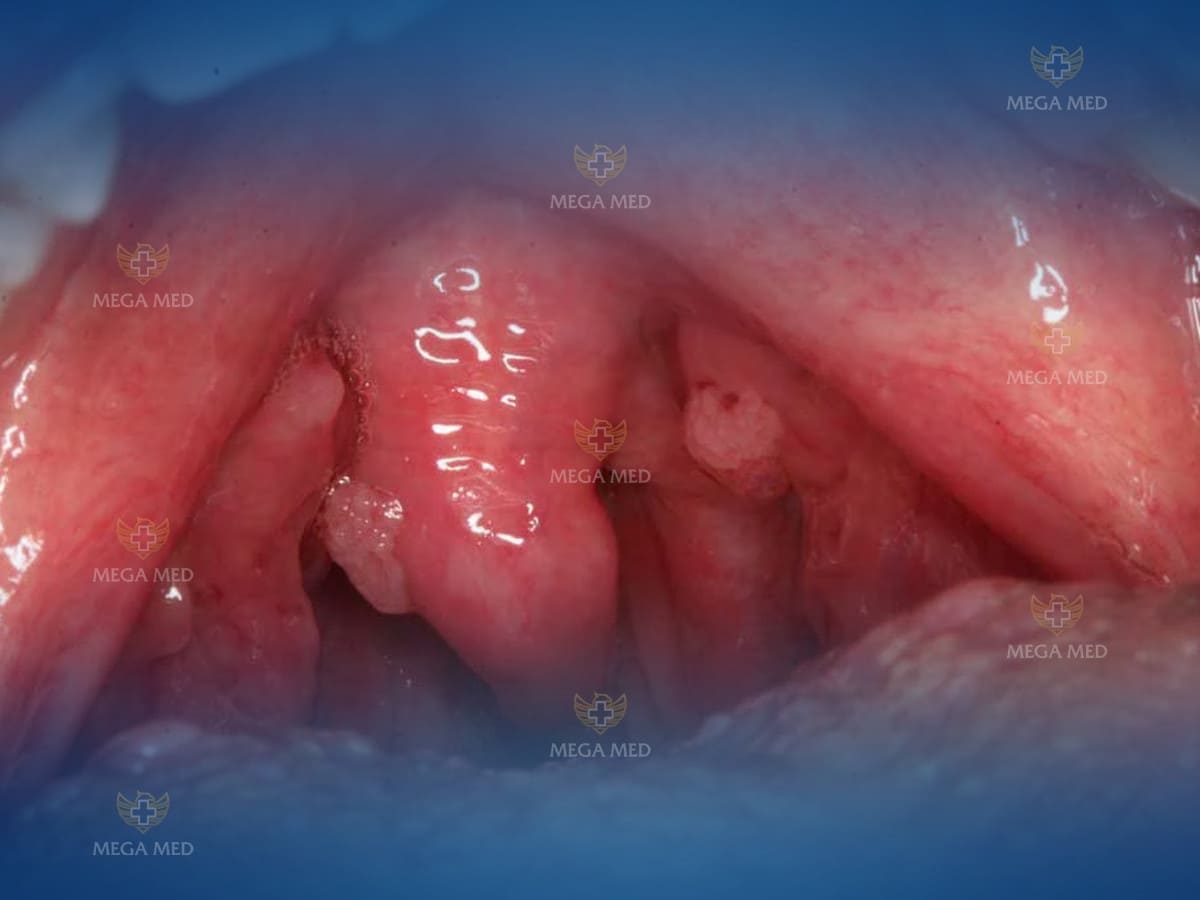

Hình ảnh sùi mào gà ở cổ họng

HPV là một loại virus gây tổn thương trên da và niêm mạc, thường xuất hiện dưới dạng mụn cóc, mụn thịt u nhú, hoặc có bề mặt sần sùi. Thông thường, các bệnh liên quan đến HPV thường xuất hiện ở vùng sinh dục và có thể ảnh hưởng đến cả nam và nữ